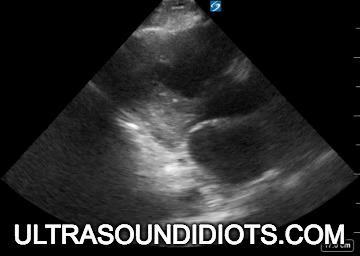

MASSIVE PE ARREST, RV DILATION AND DYSFUNCTION

MASSIVE PE ARREST

RV: RV DILATION AND SEPTAL DEVIATION

MASSIVE PE ARREST, DILATED IVC AND HEPATIC VEIN